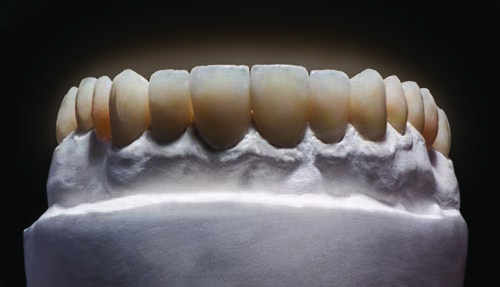

Figs. 23 and 24: After milling, the Telio CAD provisional was seated back onto the model to confirm fit and form from the labial and lingual aspects.

Fig. 28: The completed Telio CAD provisional restorations were tried back onto the model to verify fit and aesthetic qualities.